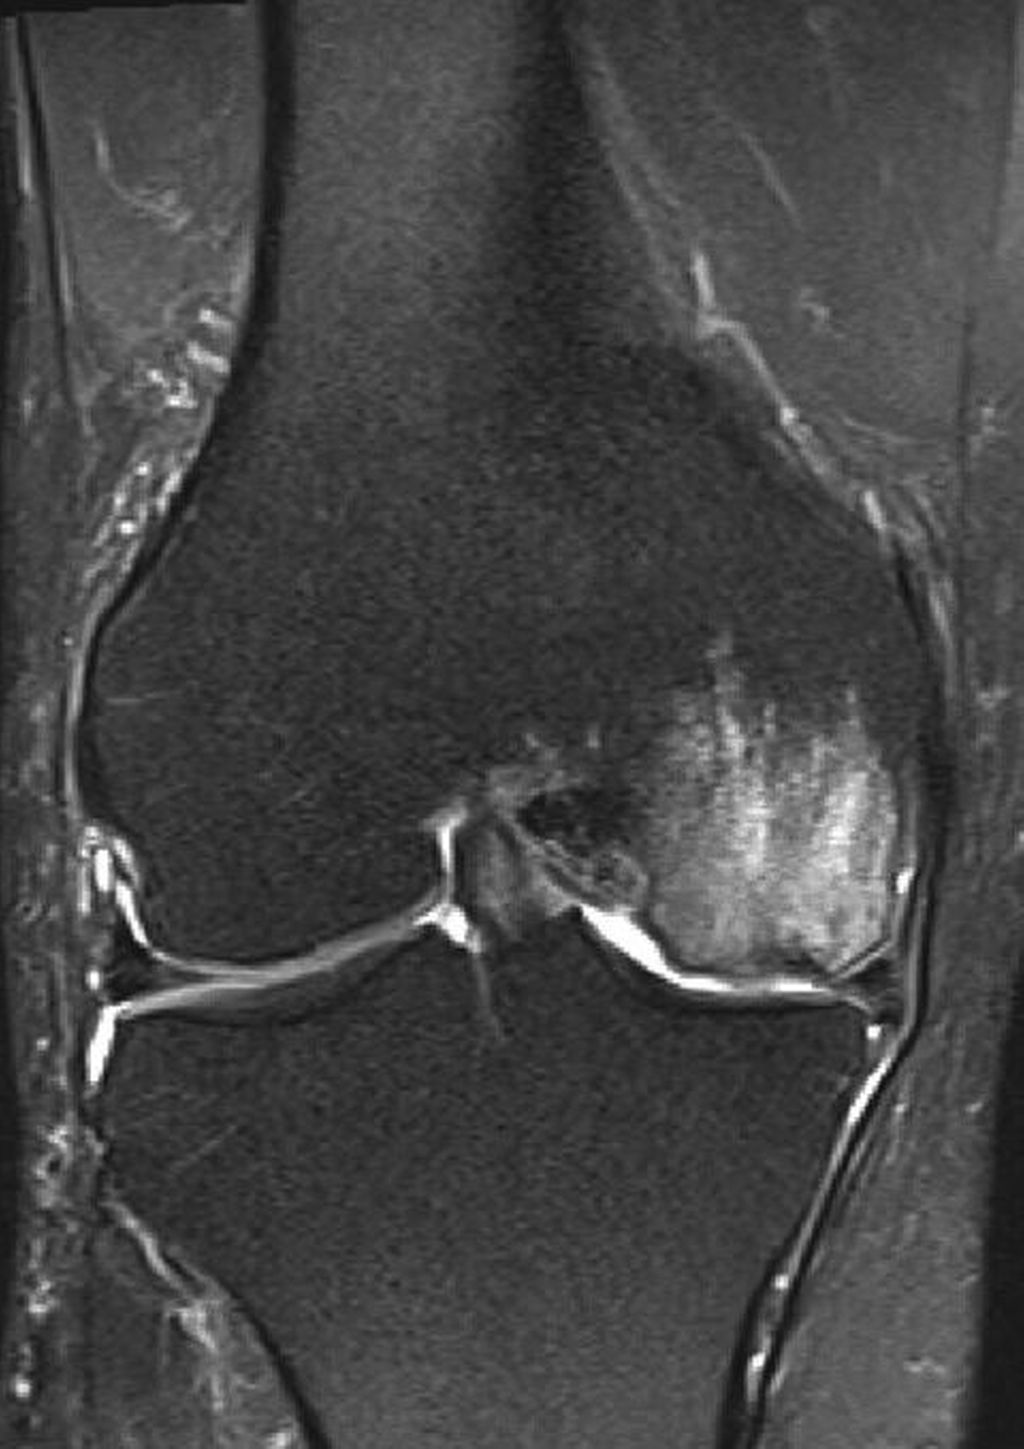

Therapieansatz unter ganzheitlicher Betrachtung des Kniegelenks

Relevanz der Beinachse bei der Therapie von degenerativen Meniskusläsionen